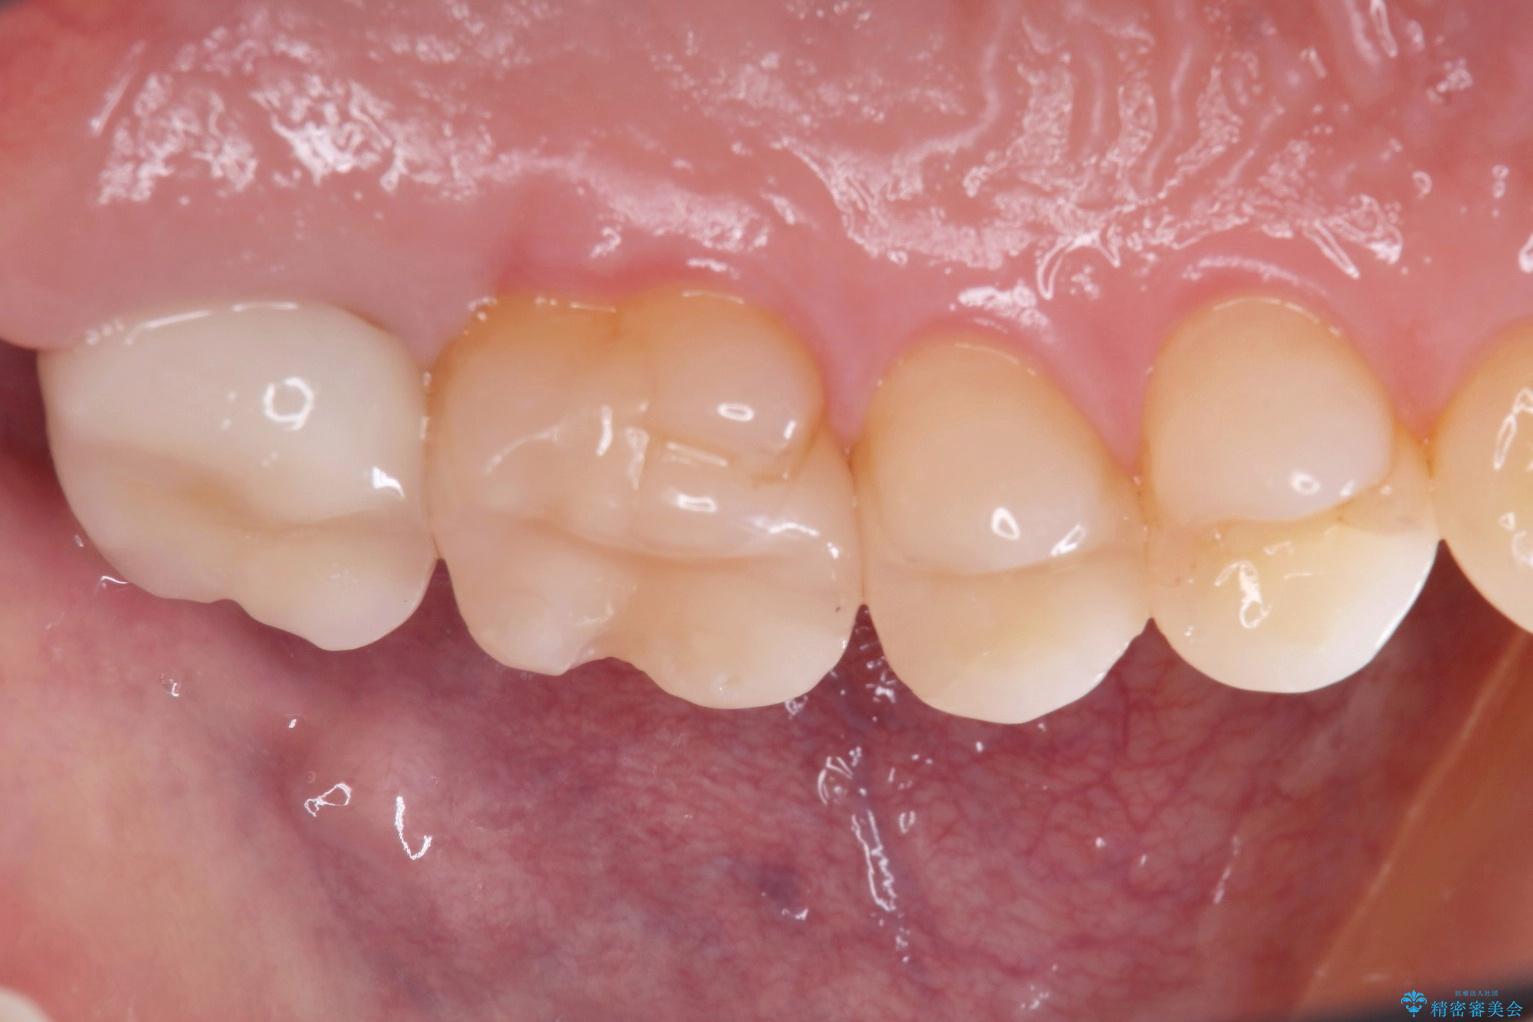

一番奥の歯は銀歯に覆われている範囲が多いため、強度などを踏まえ被せ物にしました。

その他2本は詰め物です。

銀歯が綺麗な白い歯になりました。

適合がとてもよいので、フロスの引っかかりも解消されました。